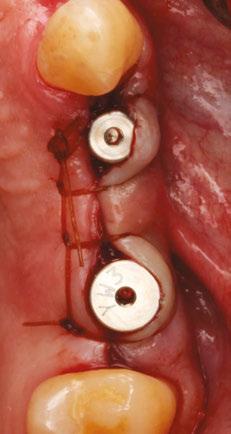

Building on the basics

Let’s review a recent case that showcases the rationale and techniques of the top three. It is common to utilize several suturing techniques in surgical closure, especially in larger grafting cases. In the following case, a lateral sinus lift was performed, and all three techniques were used to their full effect. Simple interrupted sutures are used to close small incisions and place tissue margins accurately back in place; horizontal mattress sutures are used to hold membranes in place and relieve tension over the incision line, and running interlocking continuous sutures are used to close longer incisions with watertight closure for maximum healing potential via primary closure.

A patient presented with a failing bridge on the upper left that is supported by three mini implants. The implants directly perforate the sinus and only ~2mm of residual bone height remains on the crest (Figure 8). The mini implants were removed, and a

Figures 7A and 7B: Horizontal mattress sutures are useful for helping to secure membranes in grafting situations and relieving tension in longer span incisions Figures 8A and 8B: The pre-op condition of the patient with mini implants engaging minimal bone and perforating the sinus. The patient’s implant supported bridge was loose and causing discomfort Figure 9: A periosteal biting mattress engages only the periosteum in the buccal vestibule and exit and re-enters on the lingual tissue, helping to secure the membrane tightly over the window and crest

Figure 10: Simple interrupted, papilla sling, and horizontal mattresses can be seen to achieve primary closure without any sutures over the main body of the incision. Passive closure requires that closure is obtainable without tension directly over the incision line, as seen here